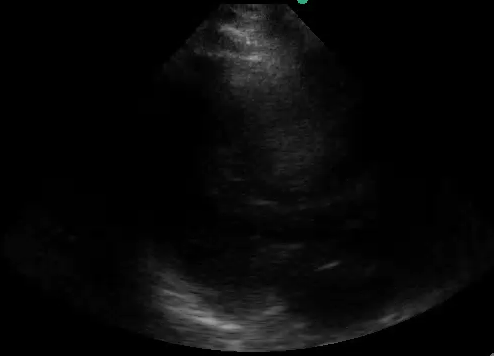

Image Acquisition: Basic Focused Assessed Transthroacic ECHO (FATE) was performed (See videos below).

Image Interpretation: Pericardial effusion was absent yet the right ventricle (RV) was dilated acutely as the RV wall thickness was normal (subcostal).  The systolic D-septum (parasternal) suggested an elevated RV afterload.  Along with the hyperdynamic left ventricle (LV) and normal left atrium (LA), there was likely a flow obstruction between the RV to LA which maybe related to the “lesion” in the RV.

The four basic cardiac views were attained though the quality varies with the apical 4 view being the least favourable with the patient in an upright position and taking rapid breaths. In practice, especially during acute situations, positioning for the ideal windows may not be feasible; and, often, not all windows can be obtained.